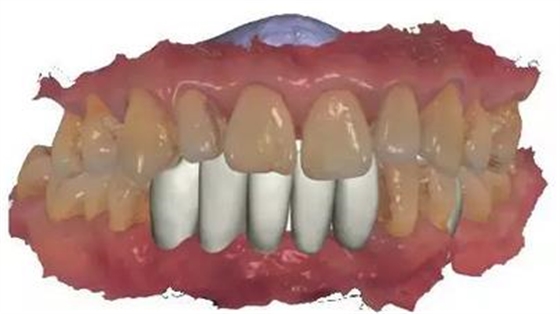

▲女性,42歲,牙周病,下前牙固定不良修復(fù)體,基牙炎癥、松動(dòng)。

▲拆除不良修復(fù)體,拔除松動(dòng)牙

▲下前牙數(shù)字化導(dǎo)板引導(dǎo)下種植后即刻修復(fù),6顆缺失牙,擬種植3-4顆

▲雙側(cè)上后牙暫不修復(fù)。

通過3shape trios口內(nèi)掃描儀掃描數(shù)據(jù)。

利用3shape導(dǎo)板軟件虛擬排牙

以修復(fù)為導(dǎo)向規(guī)劃植體

牙支持式導(dǎo)板生成

通過3Shape Dental System軟件同期設(shè)計(jì)臨時(shí)冠

手術(shù)導(dǎo)板數(shù)據(jù)發(fā)送至成都登特,通過BEGO打印機(jī)打印出導(dǎo)板,切削出臨時(shí)冠

導(dǎo)板就位后逐級(jí)擴(kuò)孔

臨時(shí)冠就位,即刻修復(fù),無咬合接觸

修復(fù)后全景片

1:本病例的難度在于高骨密度

的條件下如何順利植入植體

2:數(shù)字化修復(fù)時(shí),

種植臨時(shí)修復(fù)體可能難以就位,

特別是多顆牙的修復(fù)

來源:滿毅副教授